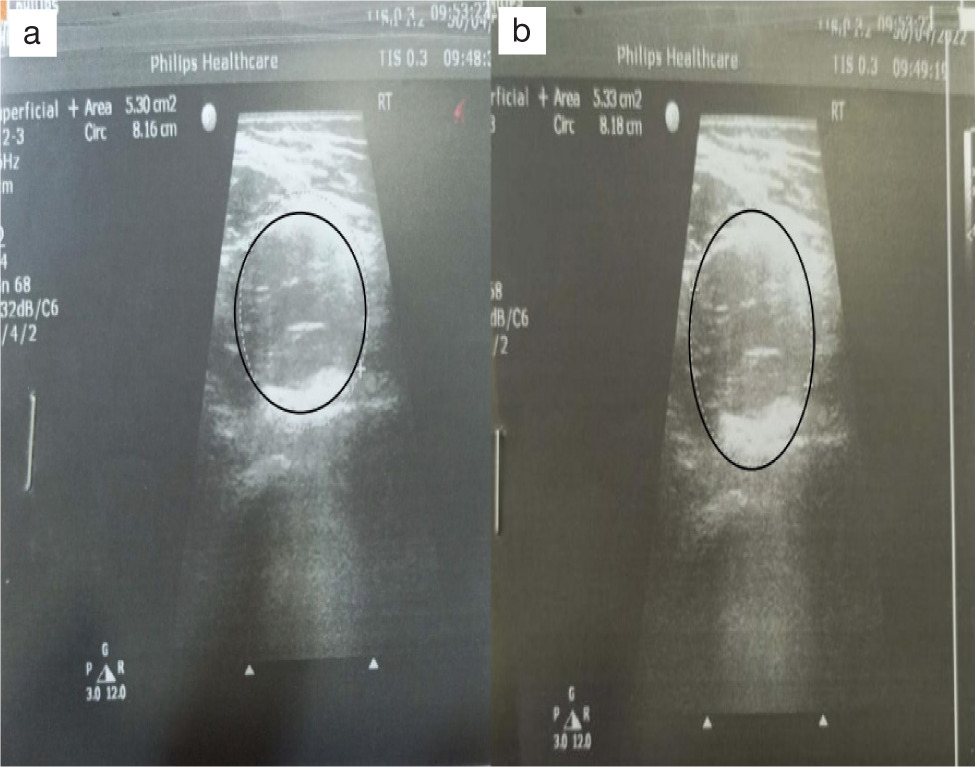

Iliopsoas muscle length using diagnostic USG: The assessment of iliopsoas length was performed by a qualified radiologist. Muscle length was measured in millimetres using a portable real-time ultrasound unit with a curved linear array transducer of 4 MHz and a water-soluble transmission gel. The imaging of the iliopsoas muscle was conducted by placing the transducer directly over the hip joint on the inguinal crease. The image boundaries were defined using landmarks like a visible crescent of echogenic brightness for the anterior femoral head and the pulsing femoral artery. For capturing images of the anterior thigh, the transducer was positioned at the level of the greater trochanter. Each muscle was imaged twice on both sides, with the probe lifted off the skin between each image [24]. For the USG, both the intra-rater reliability and inter-rater reliability interclass correlation coefficient (ICC) (2, 2) were higher for psoas muscle length [25] (Figure 3).